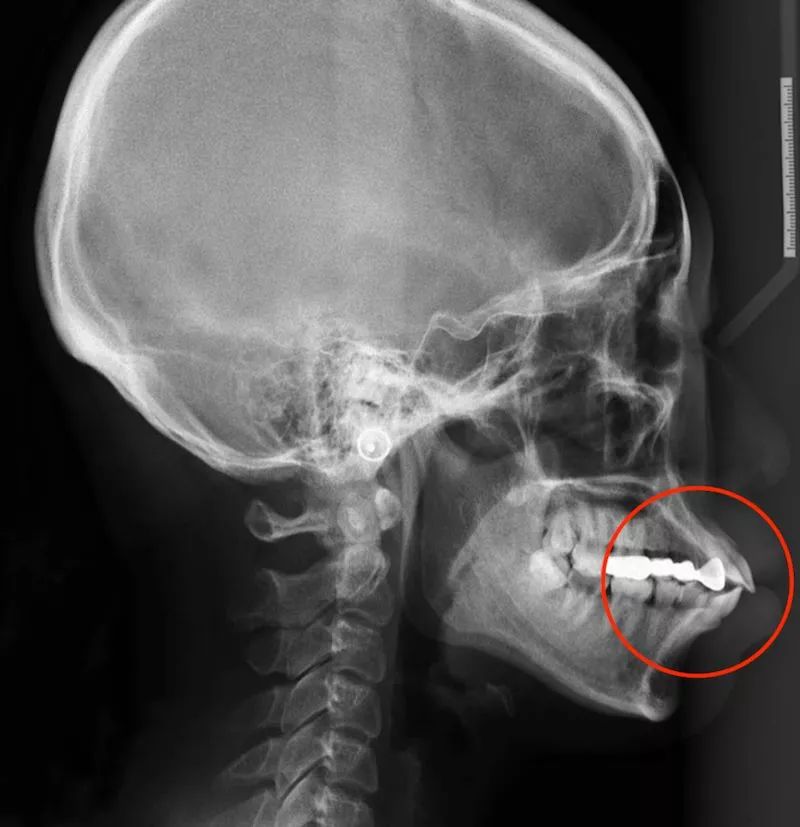

混合型的治疗方案,需要根据实际的牙齿情况以及头颅侧位片来定夺。

再告诉大家一个最省事最精准的判断方法:一切交给专业的正畸医生。医生会结合你口内牙齿的情况,以及 X 光片的情况帮你具体评估,最终告诉你一个适合你的治疗方案。